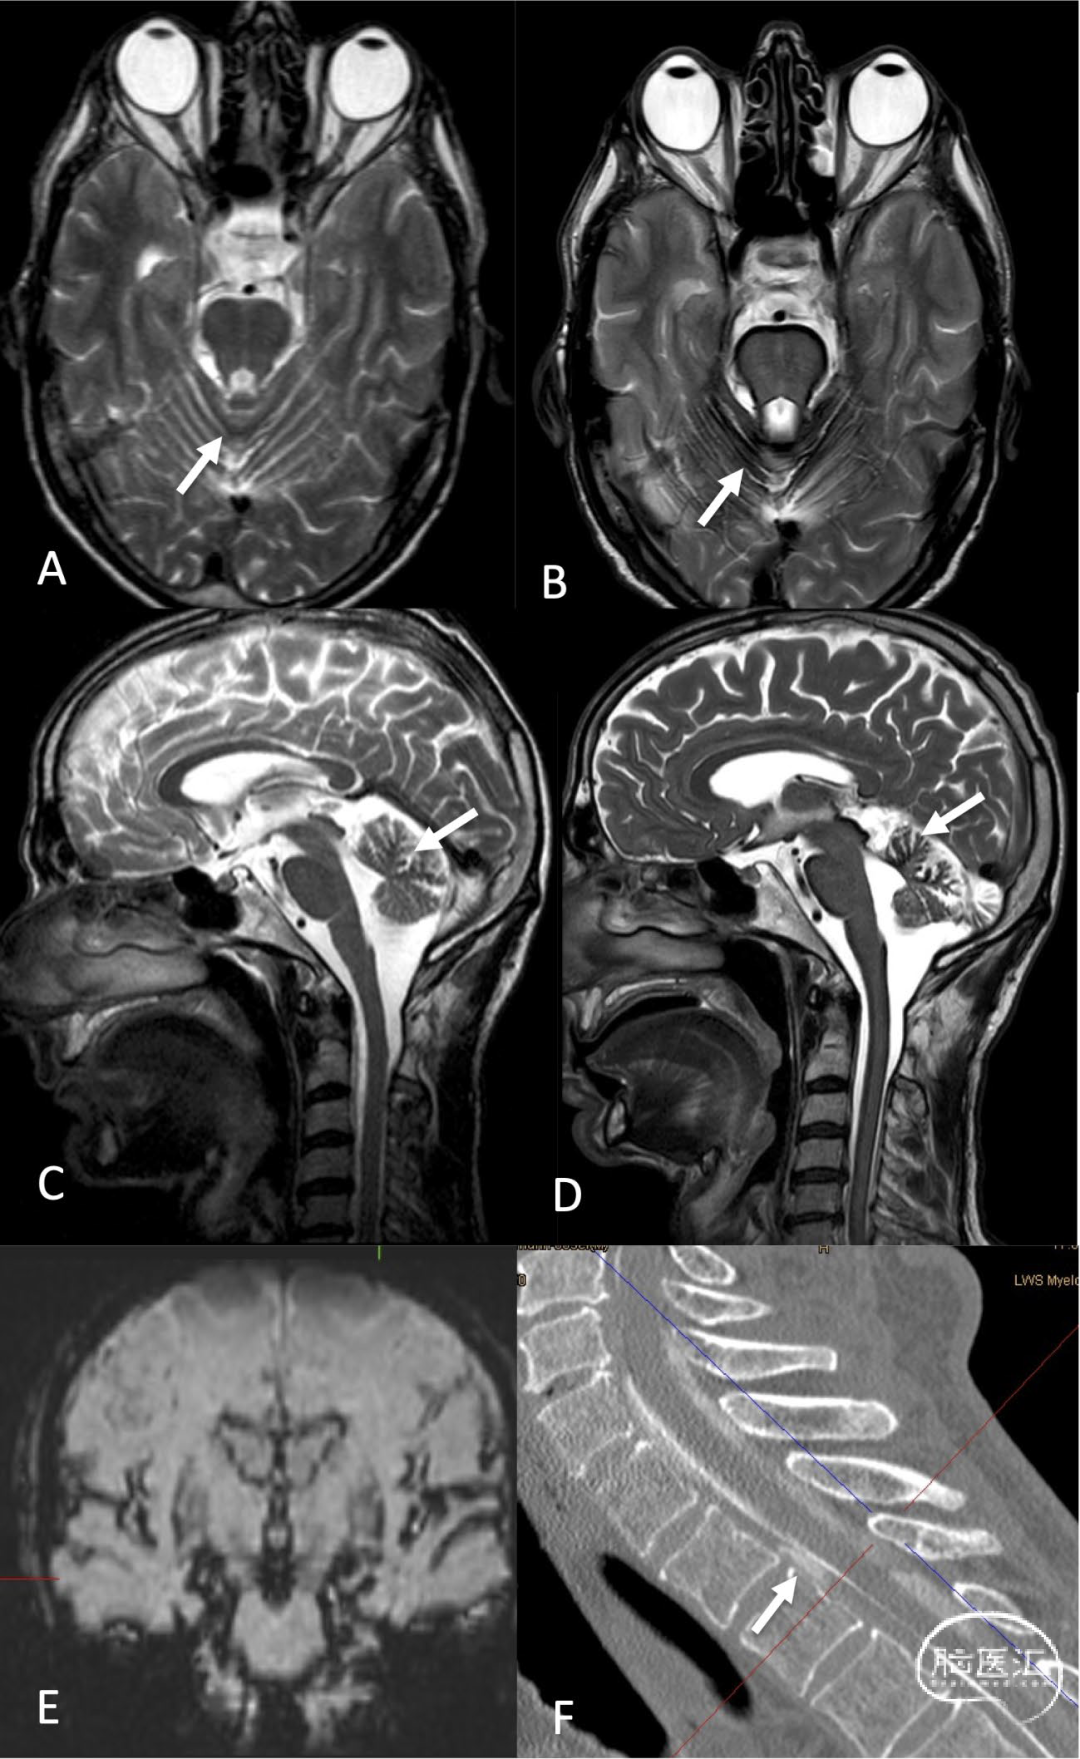

图3.男性,61岁。几年来眩晕一直在加剧。不能走楼梯,听力困难,抑郁,无法工作。直立性头痛2年后首次MRI被诊断为正常,但可见轻微的幕下含铁血黄素沉积症(A,C:箭头)。六年后,含铁血黄素沉着症和小脑萎缩有所进展(B,D:箭头)。冠状位SWI序列显示含铁血黄素沉着症(E)。动态数字剪影脊髓造影和CT脊髓造影发现T2/3腹侧可见脑脊液漏(F:箭头):